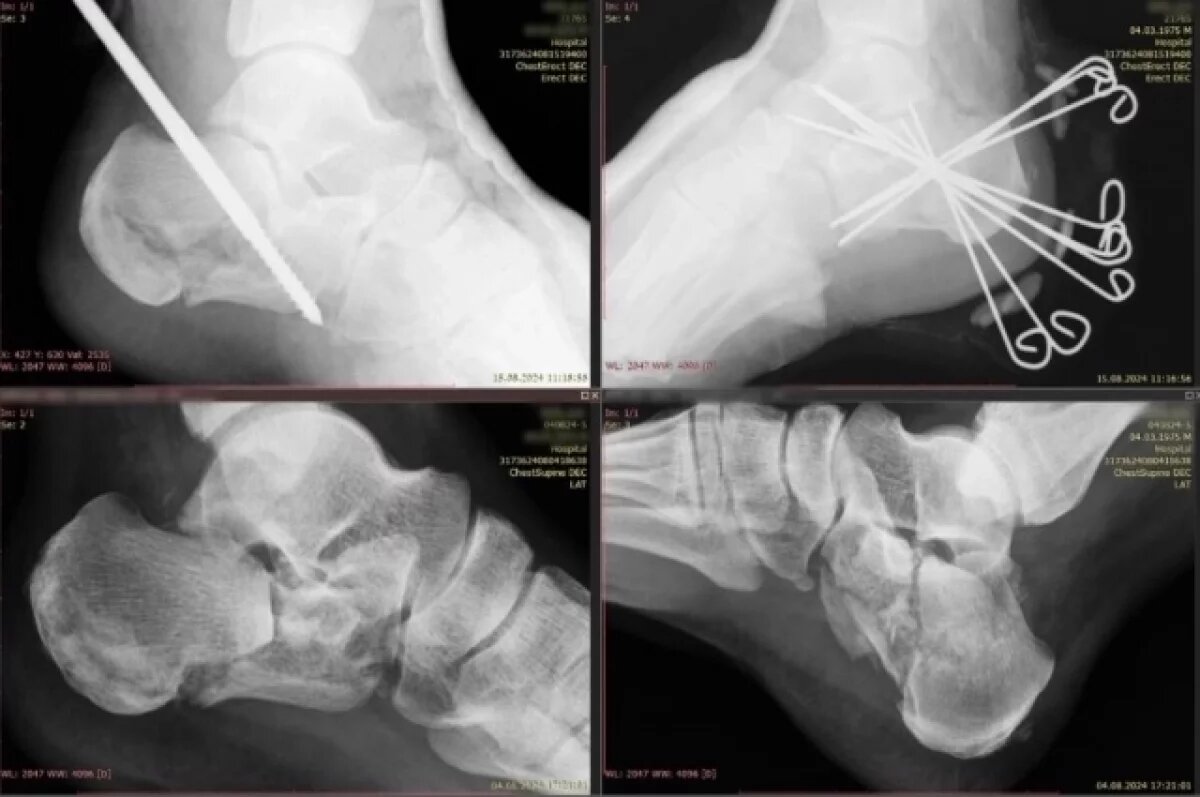

В Екатеринбурге врачи горбольницы №24 спасли молодого жителя Режа после сложной травмы. Об этом сообщает свердловский департамент информполитики. Уралец упал с трёхметровой лестницы. Из-за этого у него оказались сломаны обе пяточные кости. Он не мог ходить. Врачи его прооперировали. И потом мультидисциплинарная команда медиков успешно провела его реабилитацию. После снятия гипса он не мог ходить, на реабилитацию прибыл в инвалидной коляске. Но сейчас снова получил возможность самостоятельно передвигаться. А под бой курантов загадал желание побыстрее сесть за руль.

Уралец упал с трёхметровой лестницы. Из-за этого у него оказались сломаны обе пяточные кости. Он не мог ходить. Врачи его прооперировали. И потом мультидисциплинарная команда медиков успешно провела его реабилитацию.

После снятия гипса он не мог ходить, на реабилитацию прибыл в инвалидной коляске. Но сейчас снова получил возможность самостоятельно передвигаться. А под бой курантов загадал желание побыстрее сесть за руль.